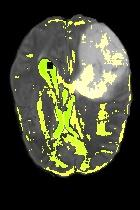

Current unsupervised anomaly localization approaches rely on generative models to learn the distribution of normal images, which is later used to identify potential anomalous regions derived from errors on the reconstructed images. However, a main limitation of nearly all prior literature is the need of employing anomalous images to set a class-specific threshold to locate the anomalies. This limits their usability in realistic scenarios, where only normal data is typically accessible. Despite this major drawback, only a handful of works have addressed this limitation, by integrating supervision on attention maps during training. In this work, we propose a novel formulation that does not require accessing images with abnormalities to define the threshold. Furthermore, and in contrast to very recent work, the proposed constraint is formulated in a more principled manner, leveraging well-known knowledge in constrained optimization. In particular, the equality constraint on the attention maps in prior work is replaced by an inequality constraint, which allows more flexibility. In addition, to address the limitations of penalty-based functions we employ an extension of the popular log-barrier methods to handle the constraint. Comprehensive experiments on the popular BRATS'19 dataset demonstrate that the proposed approach substantially outperforms relevant literature, establishing new state-of-the-art results for unsupervised lesion segmentation.